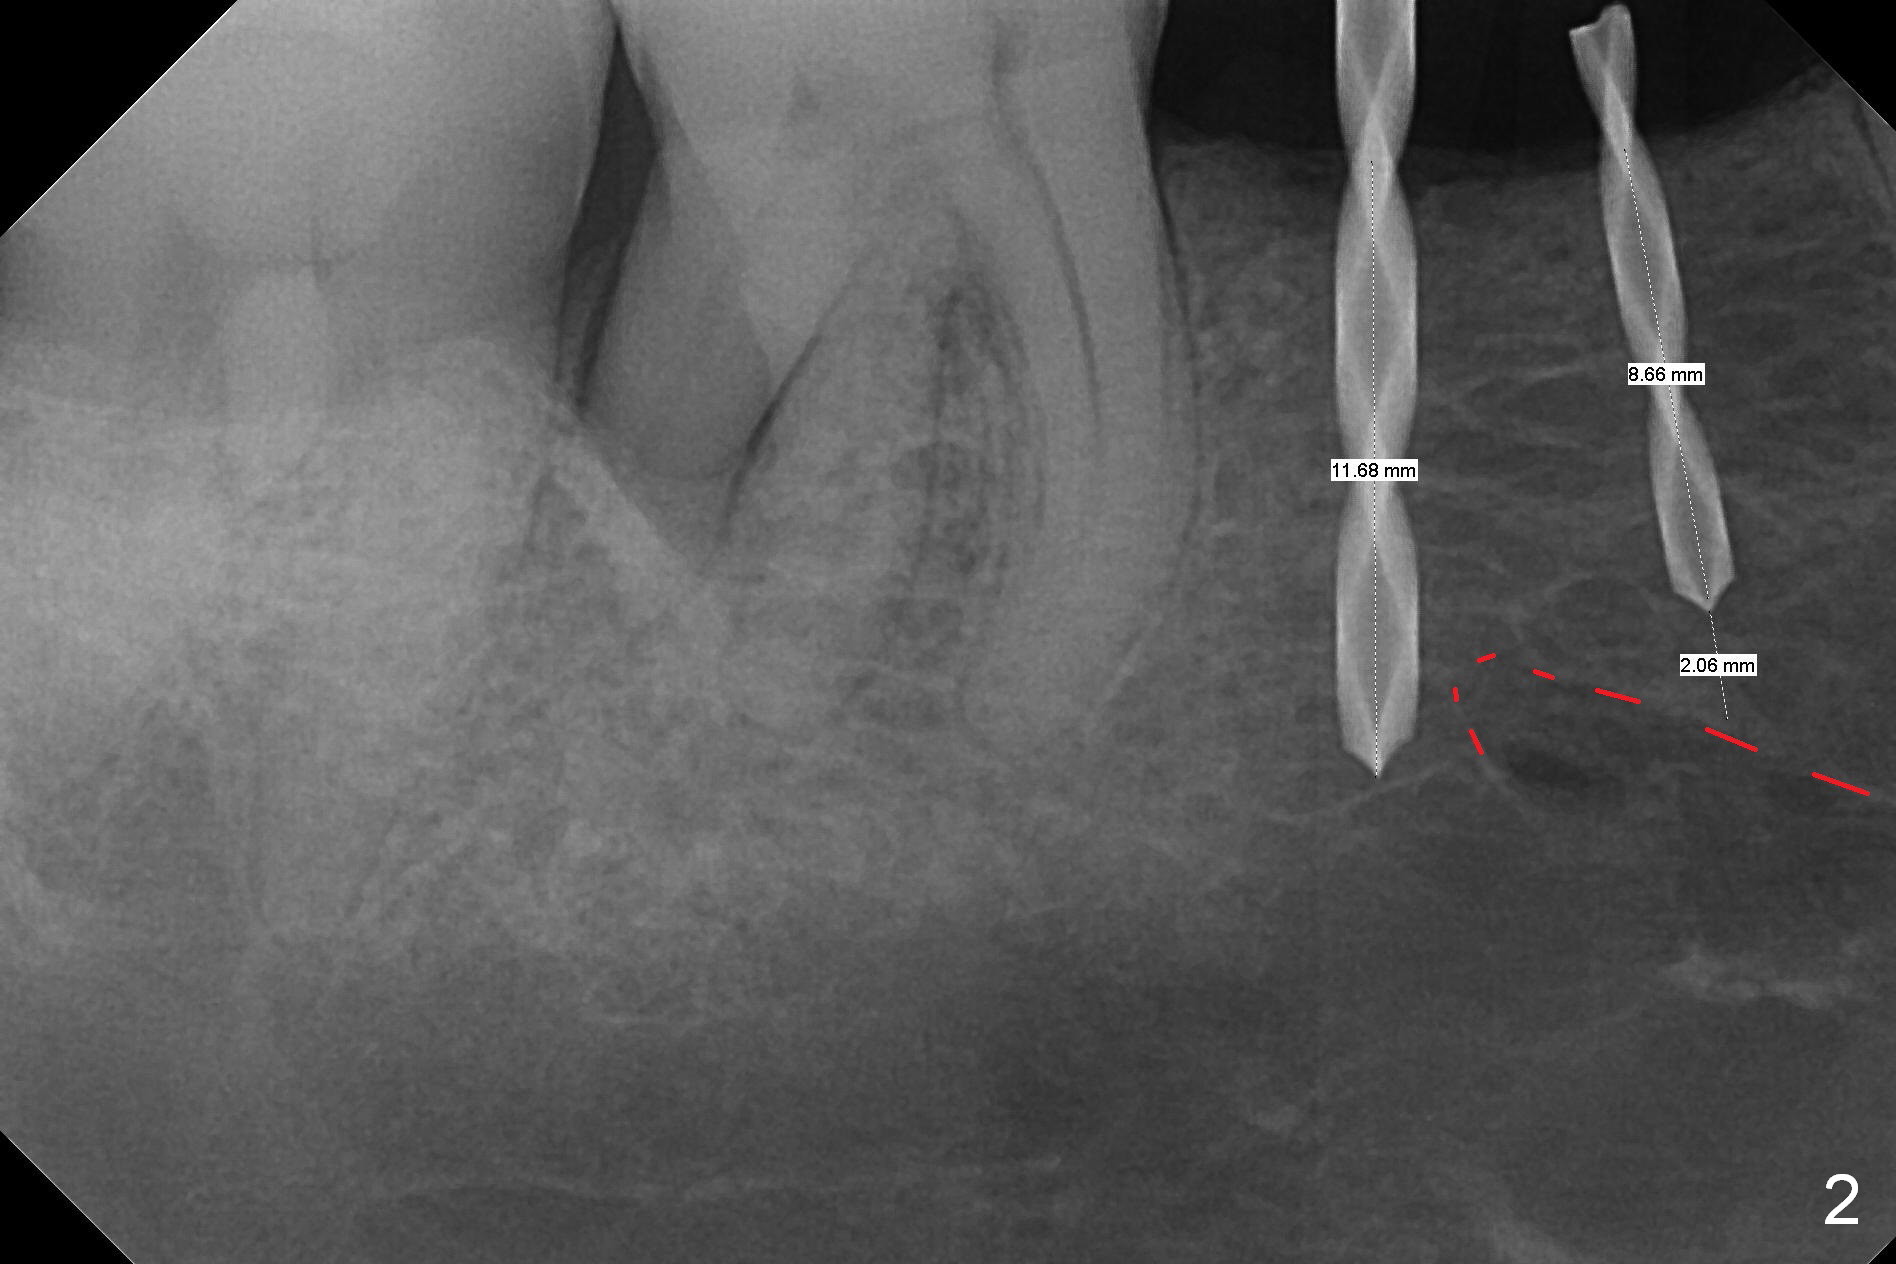

The wide mesiodistal space at #29 is most likely due to congenital missing permanent tooth (i.e., deciduous molar retention before extraction 34 years ago). The patient is now 62 years old. In fact the buccolingual width is not so narrow (Fig.1). After incision, the ridge is approximately 5 mm. Two osteotomies are established with 1.2 mm drill at 8 mm mesially and 1.5 mm one at 10 mm distally (Fig.2). The apparent approximation of the mesial osteotomy to the Mental Loop (red dashed line) is related to X-ray angulation, since there is 1-2 mm separation when two of 2x10(2) mm 1-piece implants are placed (Fig.3,4). Insertion torques of the mesial and distal implants are less than 25 and 15 Ncm, respectively. In fact bone graft is placed around the distolingual root of the tooth #30 after calculus removal (Fig.4 <). Following reduction of the abutments, periodontal dressing is applied locally. The dressing dislodged 13 days postop (Fig.5). A provisional is going to be fabricated 4 weeks postop when the wound heals (Fig.6). No bone loss is observed 4 months postop (Fig.7).